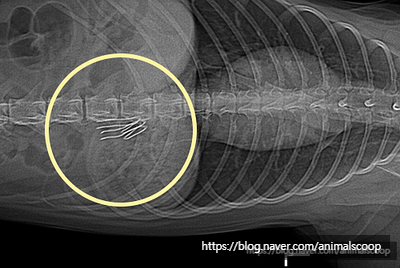

이물질의 정체를 확인하고자 진행한 엑스레이 검사 결과 율무의 위 가운데 구불구불한 철사가 있는 것을 확인했습니다. 철사와 같은 날카로운 이물질은 구토를 유발하여 제거하고자 할 경우 더 큰 문제가 발생할 수 있기 때문레 결국 율무의 개복수술이 결정되었습니다. 예상치 못한 결과에 눈물을 흘리는 보호자분을 뒤로 하고 율무의 수술이 진행되었습니다. 수술 후 율무의 위에서 이물질을 꺼내었습니다.